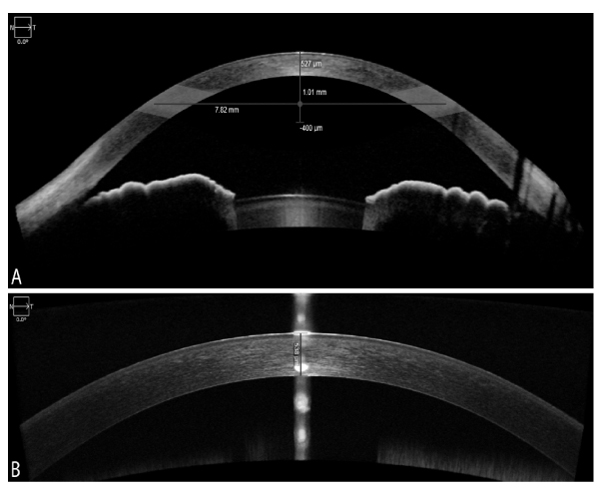

The Pentacam HR was employed to take 2 successive scans for each subject’s eye by a single examiner in one session. There was a short break between acquisitions to eliminate measurement interdependence. Apex pachymetry readings were recorded, averaged and used for subsequent CCT analysis. Images were automatically taken as soon as the Schiempflug camera was centered on the corneal apex at the pupil plane. Before each measurement, subjects were instructed to blink to create an optically smooth tear film over the cornea, and then to hold their eyes open during the image acquisition process. All measurements taken from scans with an examination quality specification of “OK” were considered valid and used for statistical analyses (Fig. 1A).

For the Zeiss Cirrus 5000 HD-OCT, high-resolution images were taken with both new external Cirrus AS lenses: the cornea-specific lens and the AC specific lens. The cornea lens attachment was used for the pachymetry map and HD cornea scans. The AC lens was used to obtain an AC scan. The Cirrus CCT was basically measured using both methods: manually with the help of the built-in calipers (HD cornea) and automated method (pachymetry map scan, AC scan). Each external lens was mounted on the OCT device with the help of a magnet for AS imaging. The HD cornea scan generates a single scan with a scan depth of 2 mm and a length of 9 mm as specified by the manufacturer. The caliper tool offered with the HD cornea scan was employed for manual measurement of the CCT Fig. (2B). It was placed on the central cornea corresponding to the hyper-reflective reflex seen on the scan (i.e. at the corneal apex), although it was challenging to place the tool precisely on the corneal apex in the hyper-reflective area.

The pachymetry scan consists of 24 radial B-scan lines (1024 samples per B-scan) with a scan depth of 2 mm. A color-coded thickness map of the cornea was generated after image acquisition and CCT from 0-2 mm sector was selected for subsequent CCT analysis Fig. (1B). The thickness was defined as the distance from a point on the anterior corneal surface to the closest point on the posterior corneal surface. The pachymetry analysis tool provided automated cornea thickness measurement in seventeen sectors. Images were captured after the horizontal single scan line was placed on the corneal apex where the hyper-reflective corneal reflex was visible. Repeat scans were taken if the initial scan was decentered or had a poor corneal apex reflection.

The AC scans generated a wide-field image of the front of the eye at the depth of 5.8 mm with A scan length of 15 mm as shown in Fig. (2A). The image provides an overall view of the AC with bilateral irido-corneal angles in one glance. The manufacturer’s software provides several automated measurements including CCT in µm, angle-angle distance in mm, AC depth in mm, and lens vault in µm.